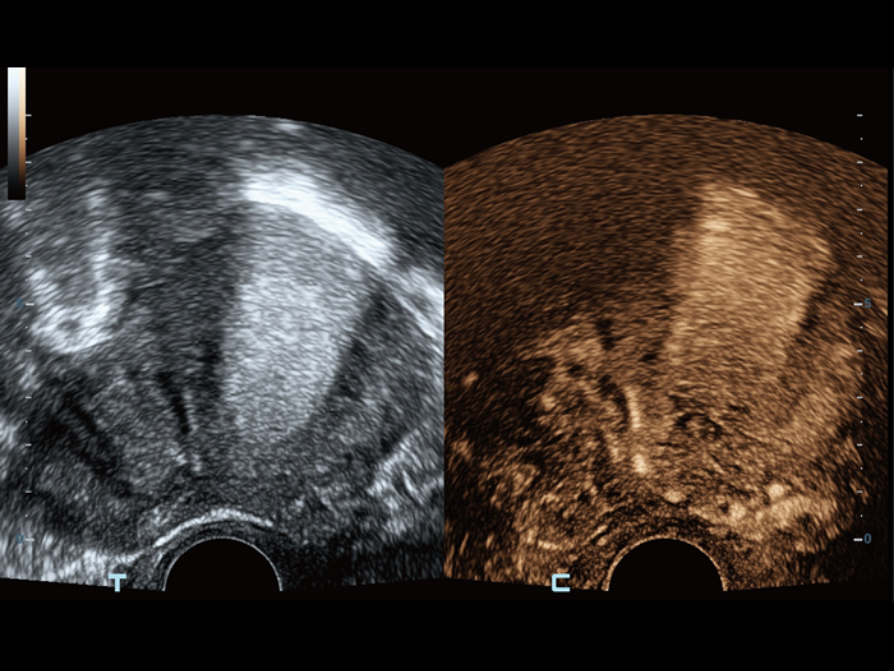

UWN+ (Ultra-Wideband Non-linear Plus) CEUS enables the Resona Series to detect and utilize both 2nd harmonic and non-linear fundamental signals, generating significantly enhanced images, resulting in greater sensitivity and longer agent duration for better understanding of the GYN diseases.